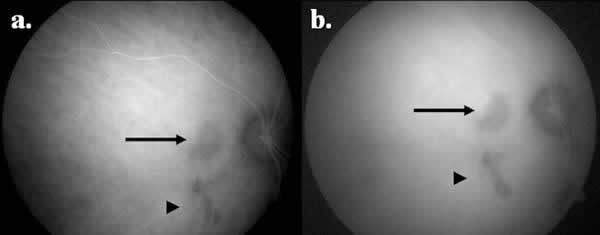

Infecciosa: históricamente la CS se ha relacionado con la infección tuberculosa y herpética (1,2,10). Desde la década de los cincuenta se reconoce la relación entre este proceso y la tuberculosis (TB), donde se pueden observar coroiditis que simulan las lesiones de la CS («tuberculous serpiginous-like coroiditis» o TB-SLC), debutando como una coroiditis multifocal con tendencia a la coalescencia en forma de patrón ameboide (8,9). Estas lesiones presentan un curso implacable pese al empleo de inmunosupresión sistémica, respondiendo de forma satisfactoria y definitiva al tratamiento antituberculoso (TAT). El mecanismo exacto que produce este cuadro es desconocido aunque parece representar una reacción de hipersensibilidad inmunomediada por el bacilo tuberculoso (11,12). Recientemente se han tratado de establecer las principales diferencias clínicas entre la CS clásica y la TB-SLC. Así, la TB-SLC suele cursar con una vitritis más intensa y lesiones multifocales distribuidas tanto en polo posterior como periferia con pigmentación variable (fig. 1), a diferencia de la CS clásica donde la vitritis es mínima o ausente y las lesiones se circunscriben al área peripapilar y macular (13). En definitiva, la TB latente ha de descartarse como primera causa de CS, dadas sus implicaciones terapéuticas y pronósticas, preferiblemente mediante la combinación de los resultados de la intradermorreacción y el QuantiFERON TB-Gold. (14) En caso de resultado positivo, es preciso iniciar una pauta de TAT, que será curativa en el caso de tratarse de TB-SLC e imperativa antes de plantear un tratamiento inmunosupresor en la CS, dado el alto riesgo de TB diseminada.

Fig. 1: Aspecto oftalmoscópico de (a) ojo derecho y (b) ojo izquierdo en

paciente con TB-SLC.